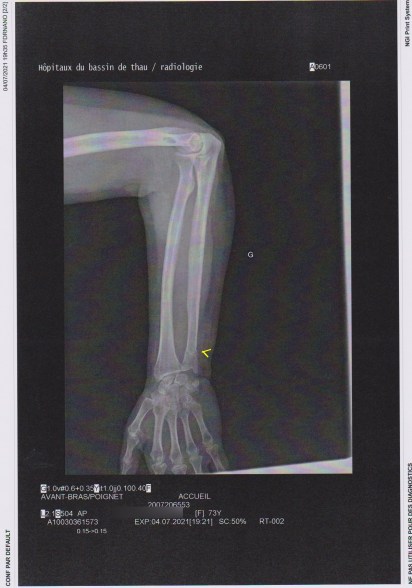

Voici la 1ère passée aux urgences, un clic dessus pour agrandir

Comme vous le voyez il y a tout juste une petite trace de fracture du cubitus. Regardez la 2ème radio maintenant